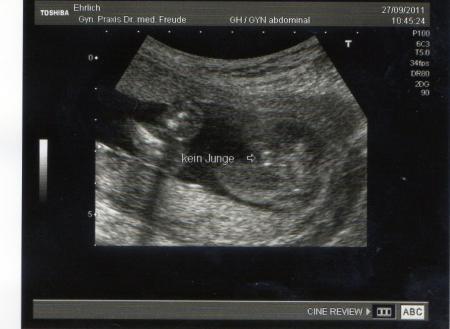

Ist zwar ein bischen unscharf, aber man erkennt es trotzdem. Sieht wohl dann wirklich nach mädchen aus oder?